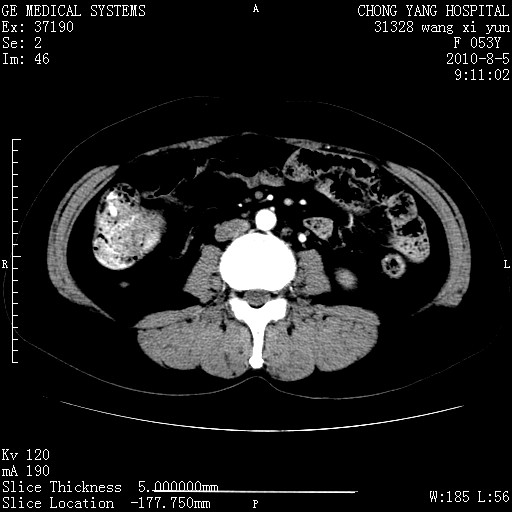

标题: CT28214:F41Y 血尿二十天,建议盆腔平扫加增强。

1)考虑肝左叶胆管细胞癌。2)脂肪肝。

支持胆管细胞ca。